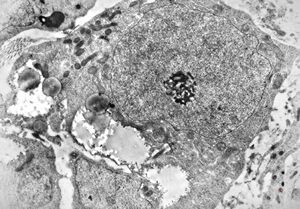

F,25y. | metachromatic leukodystrophy - n. suralis

F,8y. | metachromatic leukodystrophy - n. suralis

F,25y. | metachromatic leukodystrophy - n.suralis